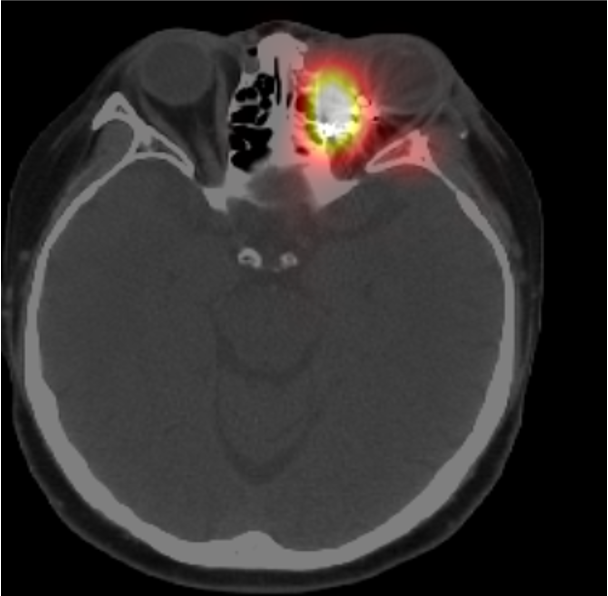

眼眶粒子植入

PET/CT引导下粒子植入

粒子植入的核心是精准植入有活性的或者代谢高的肿瘤区域才能起到治疗作用,我们创新性地将PET/CT引导投入粒子植入领域,建立国内首个PET/CT微创引导平台,将粒子优势与PET/CT强项有机融合。